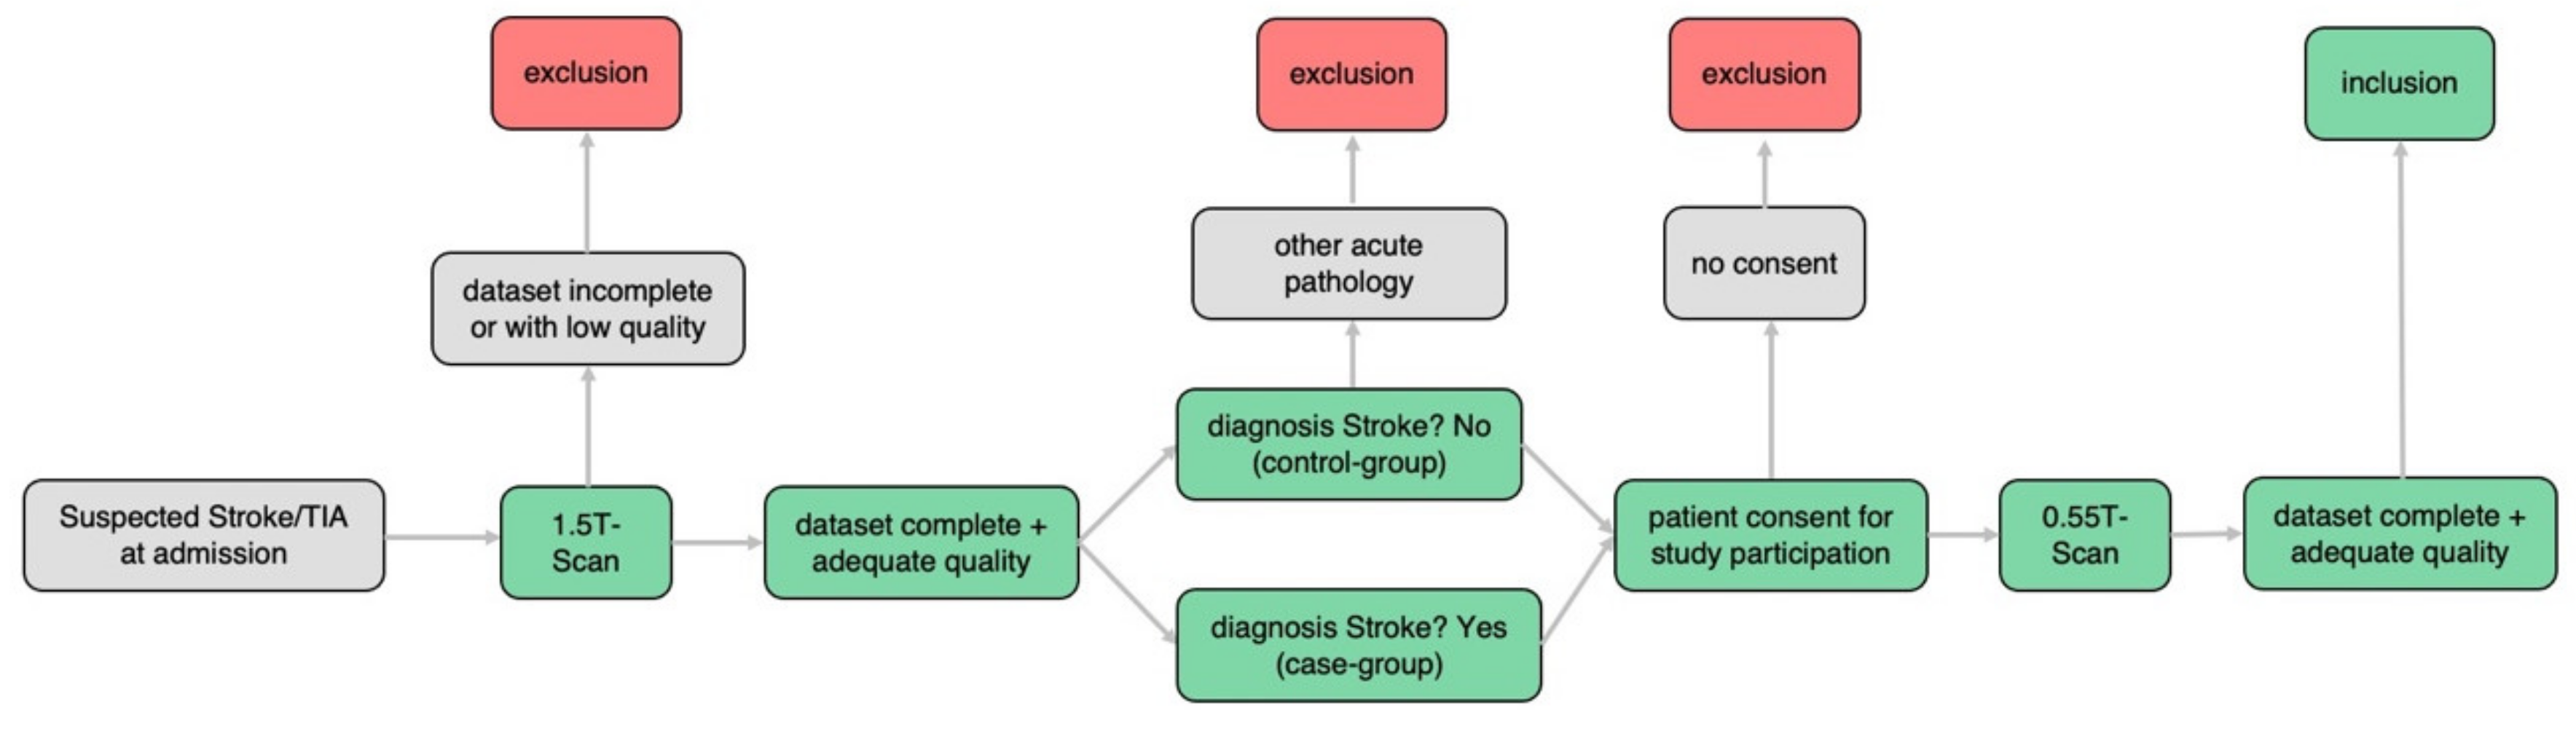

2. Materials and Methods

2.1. Patient Selection and Data Acquisition

- (a)

- Incomplete dataset 0.55T or 1.5T examination

- (b)

- Insufficient image quality 0.55T or 1.5T examination

- (c)

- No stroke but other acute pathology within initial 1.5T scan

- (d)

- No informed consent for additional 0.55T examination